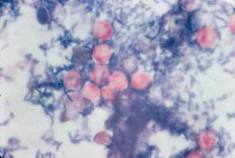

Clinical Experience in Invasive Fungal Infections: Multiple Fungal Infection as the First Presentation of HIV.

Mihon C, Alexandre T, Pereira A.

Clin Drug Investig. 2013 Feb;33 Suppl 1:37-40.